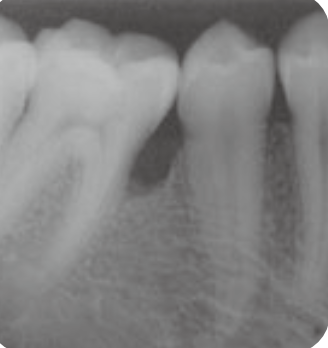

🦷 X-ray 비교

BEFORE

AFTERX-ray 상으로 명확하게 보이는 뼈 재생 효과

2Patient 2: 12개월 추적 케이스

치료 시작 전 상태

뼈 재생 완료 확인

✨ 핵심 포인트: 1년이라는 비교적 짧은 기간 내에도 명확한 치조골 재생 효과를 확인할 수 있습니다. Emdogain은 빠른 치유 속도와 함께 안정적인 결과를 제공하는 것이 특징입니다.